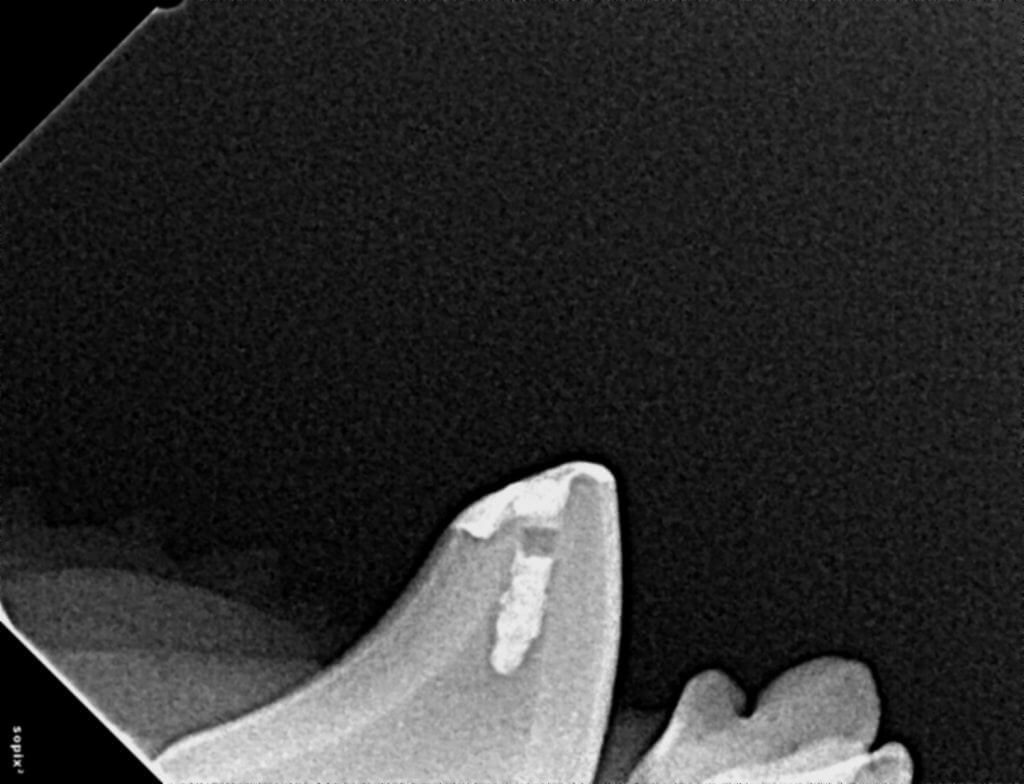

Dr. Hall begins with a thorough oral exam and dental radiographs to assess the tooth's condition. Our team uses digital X-rays and CBCT scans for detailed imaging, allowing us to identify hidden damage or infection beneath the surface.